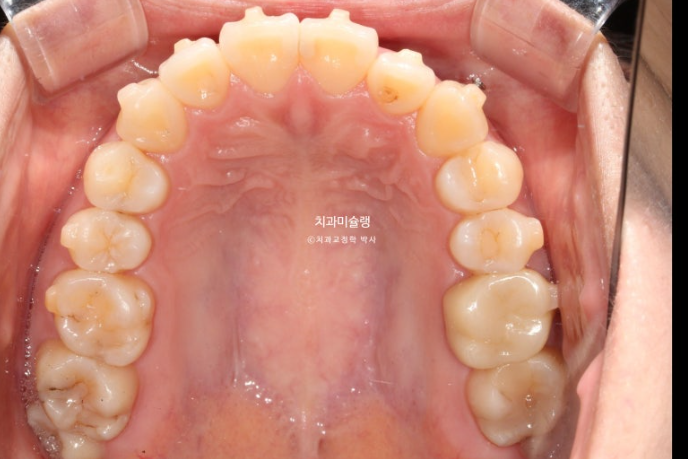

25년 9월부터 12월까지, 10개의 추가장치를 모두 낀 후 치료를 마무리 했습니다.

중심선은 완벽히 맞으며 앞니 배열과 높낮이는 교과서적입니다.

원래 좋았던 어금니 교합은 잘 유지되었습니다.

이제 전후비교 볼게요. 총 치료기간은 9개월입니다.

25.03~25.12

유지장치까지 들어간 모습입니다.